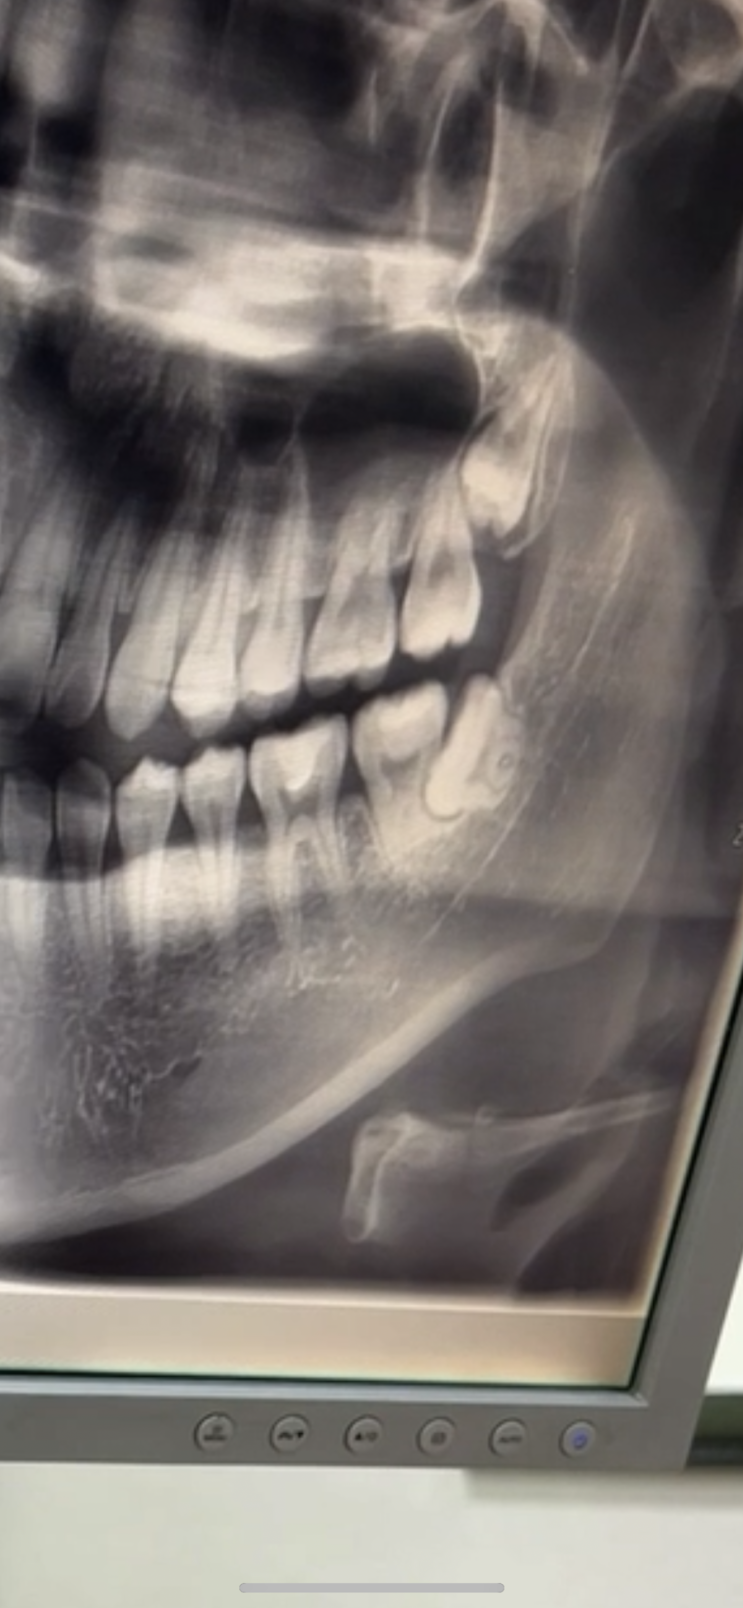

저주 받은 매복 사랑니 4개 발치 후기 | 대구경대치과 병원 발치 | 누운 매복 사랑니

매복 사랑니는 저주다 근데 그런 매복 사랑니가 누워 있다면? 매복 사랑니가 4개라면? .. 불쌍한 사람일거...